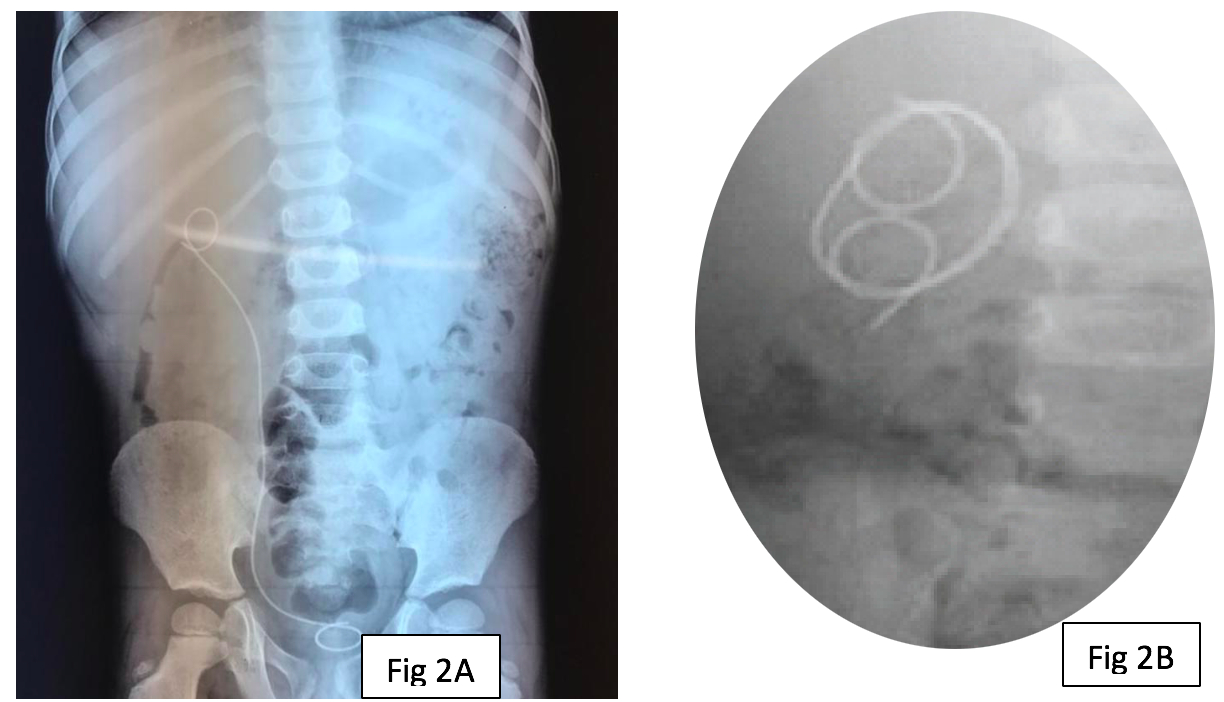

Proximal Migration of Ureteric DJ Stent: A Case Series

Background: DJ stents are routinely used in urological procedures. Rarely these may dislodge or migrate.

Case Series: Here we report proximal migration of DJ stent in three children with pelvi-ureteric junction (PUJ) obstruction treated with dismembered pyeloplasty. Ureteroscopy and retrieval of migrated DJ stents were performed in each of these patients.

Conclusion: Proximal migration of DJ stent, though rare, can cause significant morbidity and complicates it’s removal. Proper size and positioning of stent is required for pediatric patients.